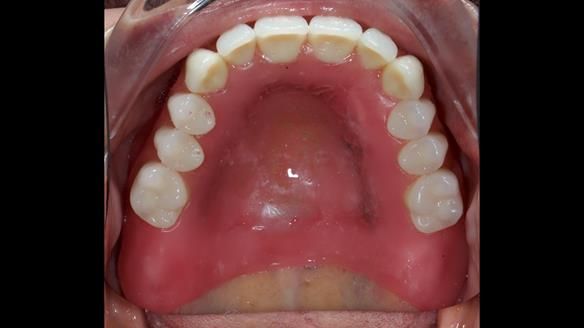

She had previously suffered from generalised periodontitis – stage IV, grade C, currently stable, with reduced attachment across the upper arch.

By the time she came to me, her periodontal condition was stable — but the aesthetics in the upper jaw were very poor.

We provided her with an immediate upper denture (Mk 1), followed by a definitive metal-based upper denture (Mk 2). A lower removable partial denture was discussed, to be made only if needed once the upper treatment was complete. However, at review, this wasn’t necessary — Adnana had excellent neuromuscular control and function, even with a shortened dental arch (SDA).